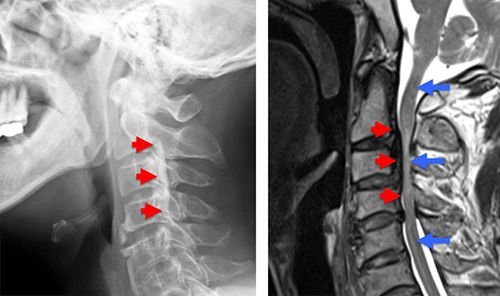

図1 後縦靭帯骨化症(OPLL)患者の写真

頸椎(首の部分)の側面から見たX線像(左)とMRI像(右)。赤矢印がOPLL。OPLLが脊髄(青矢印)を圧迫している(上下に比べて、脊髄が細くなってしまっている)。